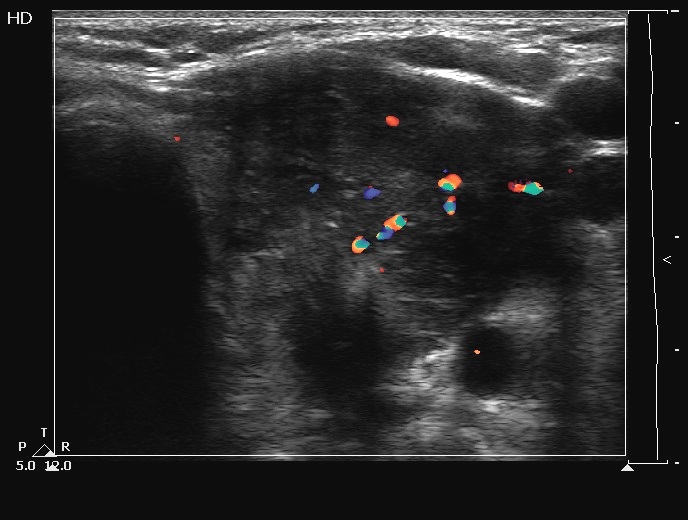

Ultrasonography. The thyroids were echonormal and contained several cystic areas and an echonormal nodule in the right lobe. There was a large partly echonormal, partly hypoechogenic nodule in the left thyroid. This lesion had irregular bordersr and presented an irregularly increased intranodular vascularization.